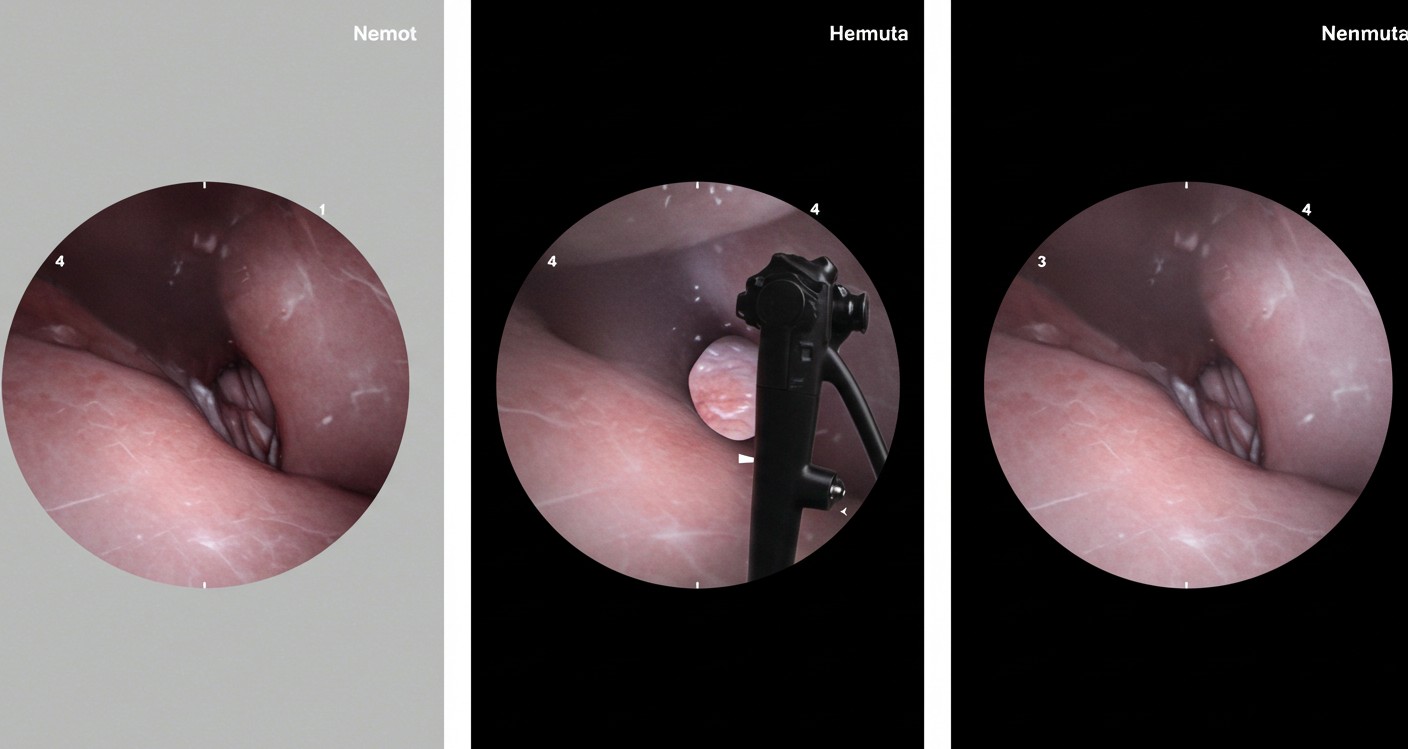

• 검진 방법: 위내시경 권고 (기본 검진 방법으로 확정)

• 특수 대상: 고위험군과 고령층에 대한 맞춤형 전략 강화

이는 위내시경이 조기 위암 발견에 가장 효과적이라는 국내외 연구 결과를 반영한 것입니다.